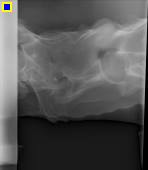

And so we began the X-rays, Pirate understood perfectly well what was going on and stood rock still for over an hour for 15 different X-rays on his stifle, back and neck.

Now here comes the amazing part of Pirates story after going over all the X-rays, from all angles, this was Dr Owens diagnosis. During the car accident, Pirate had suffered a broken neck and a fractured stifle. The amount of pain he must have been in while alone is unthinkable. Through the healing process visible on the pictures, Dr Owen guesses the accident took place approx a year ago. Pirate is a living breathing miracle.

Dr Owen himself said the only way the broken neck had healed was Gods work, that Pirate suffered no neurological damage (in fact quite the opposite) is Gods work. Pirates fractured stifle has healed, and will get stronger as he gets stronger. The body will, eventually heal itself.

Wow, this was a lot to take in. What a brave spirit this boy has!! If he wouldn't give up why should we? If Pirate was a human, he would have a simple knee replacement, being equine, the operation is beyond our financial means and we don't think it would make a huge change for him, the fracture has healed and Pirate is not in demanding work other than to tote a child around occasionally, he does most of his exercise alone bucking and galloping free. The only time Pirate needs meds is a couple of days before the farrier comes for him, this makes it easier for him to lift his leg, and we position him so its comfortable for him.